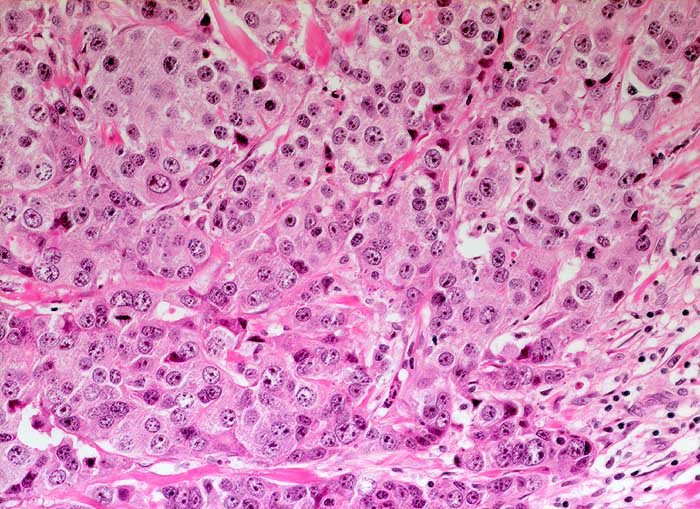

Einleitung

Das invasive Mammakarzinom zeigt zytologisch eine homogene Population maligner Zellen. Typischerweise sollten die Ausstriche zellreich sein und alle vorhandenen Zellen sollten maligne aussehen. Wenn man atypische Zellen suchen muss, ist der Ausstrich nicht diagnostisch für ein Karzinom, kann aber gleichwohl verdächtig sein. Die malignen Zellen sind in lockeren Gruppen gelagert und viele liegen einzeln. Crowding, Zellkannibalismus und Kernmolding sind gute Hinweise auf Malignität. Myoepithelien sind meistens aber nicht immer abwesend. Mammakarzinomzellen sind eher monomorph und deutlich grösser als normale duktale Epithelien. Zellkerne, die grösser sind als zwei Erythrozytendurchmesser, sind tumorverdächtig. Fast immer sind Kerbungen der Zellmembran nachweisbar. Das Chromatin ist im Gegensatz zu anderen Adenokarzinomen fein granulär und gleichmässig im Kern verteilt. Nukleolen sind meist unscheinbar. Makronukleolen sprechen für ein invasives Karzinom.

Die Kohäsivität ist das wichtigste Kriterium zur Feststellung des Differenzierungsgrades. Bei hoch differenzierten Karzinomen finden sich Verbände, bei wenig differenzierten liegen die Tumorzellen vermehrt einzeln. Wenig differenzierte Karzinome zeigen gesteigerte Kernatypien und der Hintergrund ist eher detritisch aufgrund ausgedehnter Tumornekrosen.

Unten werden Beispiele von einem hochdifferenzierten und einem wenig differenzierten Mammakarzinom gezeigt.